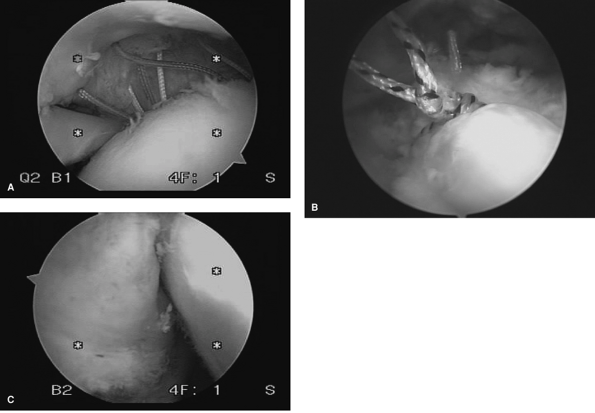

tear is delineated arthroscopically. The entire visualized cuff should

be palpated and delineated for any significant intrasubstance

delamination (Fig. 38-3).

|  |

| Figure 38-3 Intrasubstance delamination of a rotator cuff. A: MRI (T1) view of an inner surface delamination. B: Intra-articular visualization of this significant lesion. |

| Figure 38-4 Preparation of the cuff tissue and the footprint of a partial-thickness tear. Right shoulder, posterior portal view. Note the anchor already in place at the anterior edge. |

| Figure 38-5 Suture penetrator being used for grasping a suture directly from the anchor after piercing the rotator cuff tissue. |

are now passed through the tissue. Various suture-passing devices are

available for this process, and they include needle-type devices with

various curvatures and cannulated centers that allow suture shuttling

through the appropriate point in the cuff. In addition, other

penetrating devices allow for piercing the cuff tissue directly and

grasping the suture (Fig. 38-5).

space is again visualized from posterior and the knots are tied in a

methodical fashion from anterior to posterior (Fig. 38-6). The basic principles of knot tying should be followed, namely a sliding locking knot that is backed up with reverse

half hitches. In addition, only one pair of sutures should be in the

portal while tying is taking place at any one time to avoid tangling of

sutures.

| Figure 38-6 Sutures passed following anchor insertion (Right shoulder, posterior portal view). A: Intraarticular visualization of the final suture position. B: Subacromial visualization of the final sutures. C: Final intraarticular visualization of the cuff repair. |